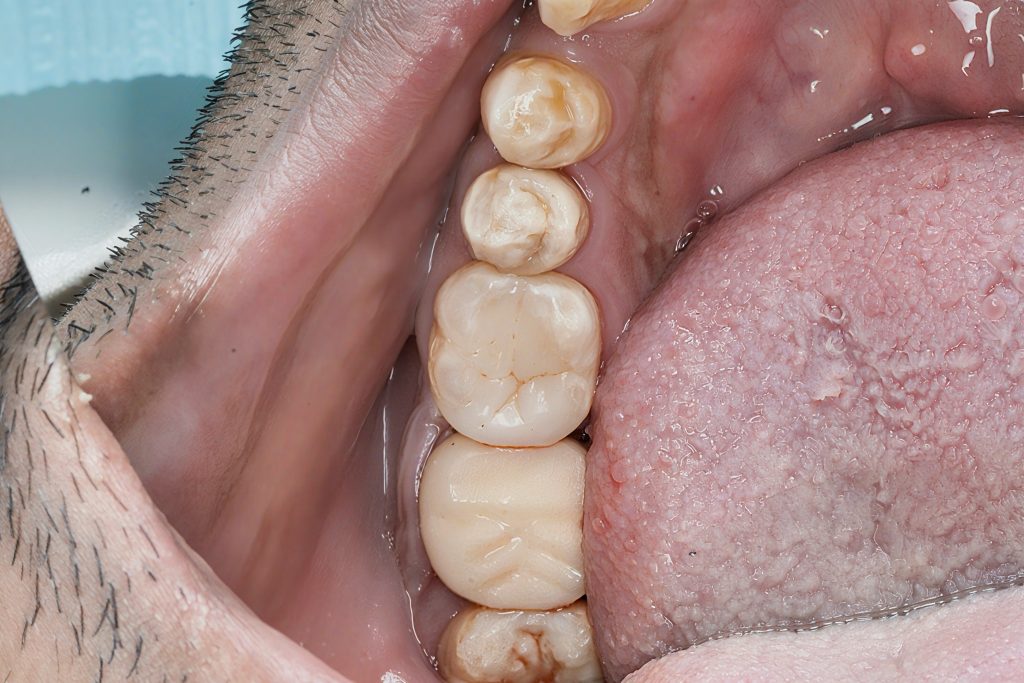

The tooth presented with a large carious lesion extending sub-crestally on the distal, compromising the marginal integrity and leaving no clean, dry, enamel-based margin for adhesive bonding. A single-visit root canal treatment was completed, followed by a staged Deep Margin Elevation (DME) to relocate the margin supragingivally. The case was finished with full cuspal coverage using a biomimetic composite onlay under rubber dam isolation.

End result: a strong, functional, biomimetic onlay that blends seamlessly with the adjacent dentition.

- Excellent occlusal morphology, contact tightness, and natural enamel optics.